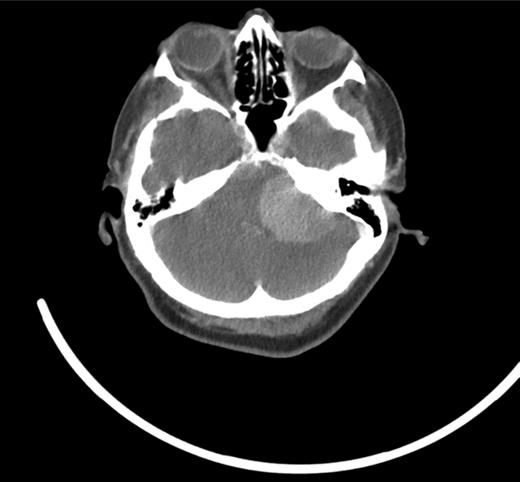

Urgent skull base to diaphragm computed tomography (CT) scans (Fig. 1) suggested a large (4 × 3.5 cm) mass within the left posterior fossa and no lung lesions. There were no changes to the pre-existing renal cysts.

CT scan—large (4 × 3.5 cm) mass within the left posterior fossa.